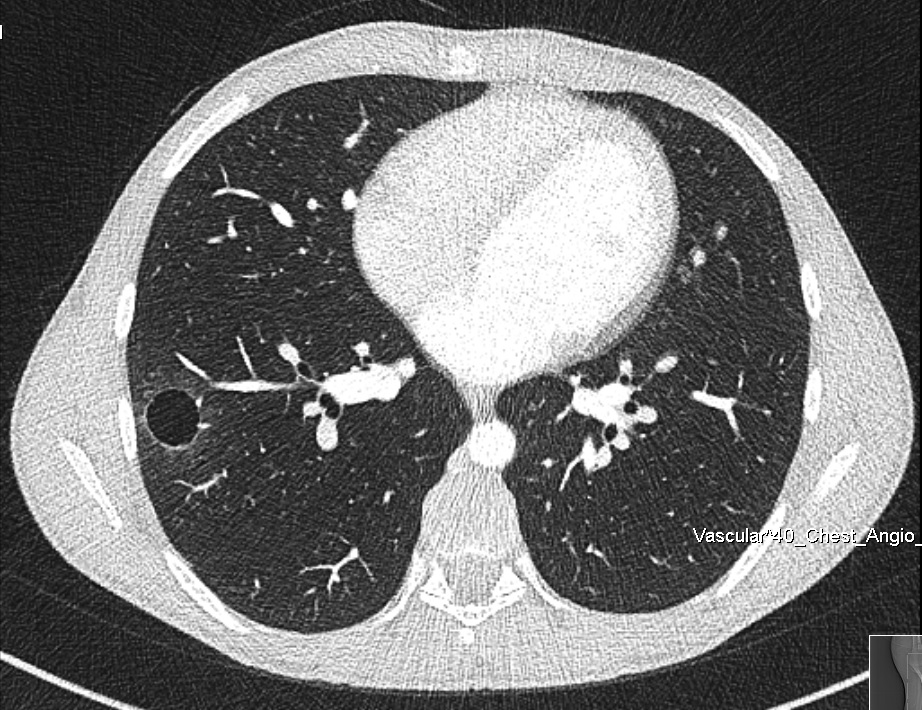

Figure 1. Chest CT scan.

Inflammatory myofibroblastic tumors (IMT) are relatively benign tumors that can occur in the lung, and also arise from different anatomical locations. In the lung, an IMT can be a solitary pulmonary nodule or a locally invasive lesion. The authors share the case of a 15-year-old male patient who presented with occasional hemoptysis. A chest computed tomography (CT) scan showed a cavitary lesion in the right lower lung lobe. A thoracoscopic segmental resection was performed, and the pathological result was an IMT. To the best of the authors’ knowledge, there are very limited reports of a lung IMT presenting as a cavitary lesion in the English literature.

The authors report on the case of a 15-year-old male patient who presented with a two-year history of recurrent hemoptysis (about 60 ml), occurring once every three to four weeks. The hemoptysis was not related to physical activity or other respiratory symptoms and was self-limiting. The patient underwent a diagnostic fiber optic bronchoscopy that was inconclusive. A chest CT scan showed a cavitary lesion in the right basomedial segment of the right lower lobe of the lung. The patient's case was discussed in a multidisciplinary board meeting, and it was agreed that the right lower lobe lung lesion was the most probable cause of the patient's condition. The team planned a thoracoscopic uniportal video-assisted segmental resection of the right basomedial segment of the right lower lobe. The operative course was uneventful. The chest tube was removed three hours after the surgery, and the patient was discharged home on postoperative day one.